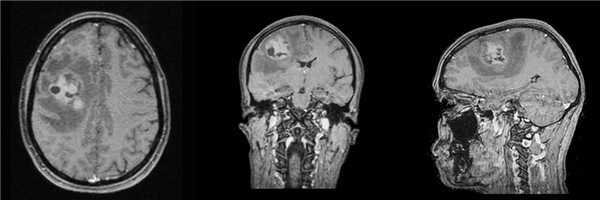

Пациентка 32 лет в течение месяца отмечает появления головной боли, сопровождающейся тошнотой и головокружением. Консультирована неврологом, направлена на МРТ, при которой выявлена внутримозговая опухоль правой заднелобной области, накапливающая контрастное вещество, с выраженным перифокальным отеком.

Пациентке проведена операция - микрохирургическое удаление опухоли правой лобной доли с использованием интраоперационного нейрофизиологического мониторинга.

Гистологический диагноз - морфологическая картина и иммунофенотип в большей степени соответствуют анапластической плеоморфной ксантоастроцитоме, WHO Grade III.

Молекулярно-генетическое исследование мутационного статуса методом ПЦР в режиме реального времени мутации гена BRAF V600E не выявлено.

При контрольной СКТ данных за остатки опухоли/послеоперационные осложнения не получено.

В послеоперационном периоде отмечается появление легкой асимметрии лица за счет левой его половины, практически полностью регрессировавшее к моменту выписки из стационара на 6 сутки.

При контрольной МРТ с контрастным усилением через 2 месяца данных за остатки опухолевой ткани не получено.